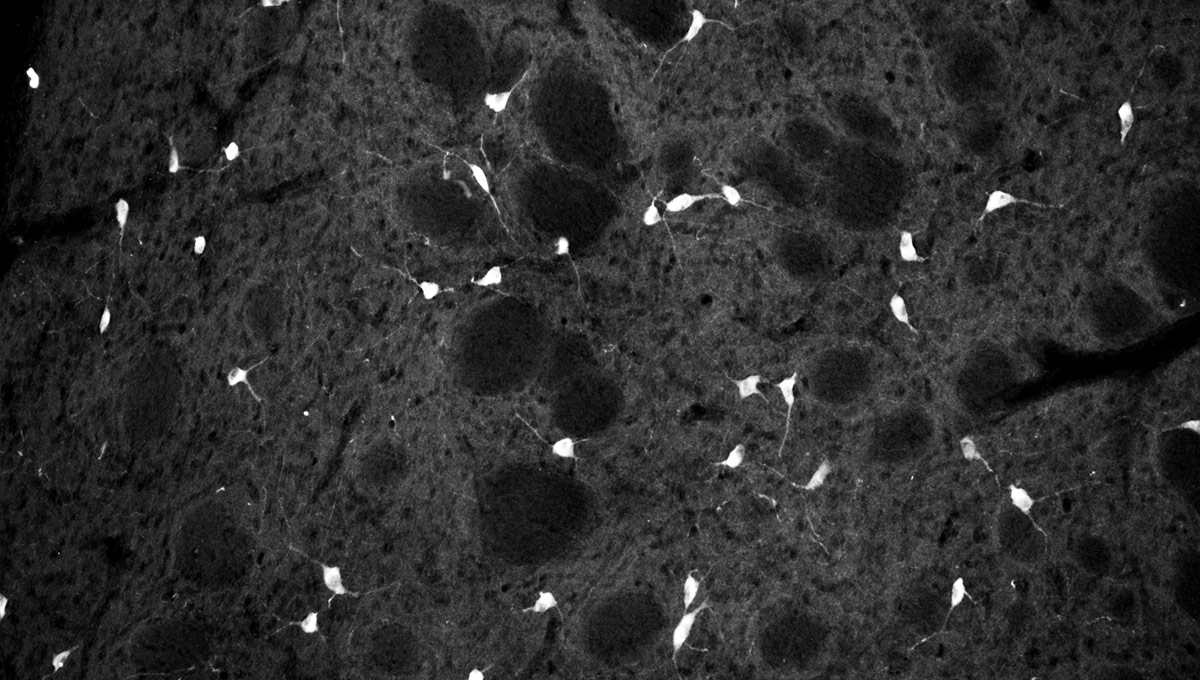

The green microscope image featured above is from Matthew Holahan’s experiments and shows the accumulation of a protein called alpha-synuclein in a mouse brain; the bright spots show alpha-synuclein aggregating into clumps of spaghetti-like filaments that, researchers believe, lead to decreases in dopamine and Parkinson’s symptoms such as slow movements, tremors and rigidity. The red image shows A-syn-1, the aptamer Holahan and Maria DeRosa designed to target the protein. The yellow image shows the successful co-localization of A-syn-1 and alpha-synuclein, which has the potential to help stop Parkinson’s disease. The black-and-white images, in order of appearance from top to bottom, show: dopaminergic neurons in the substania nigra, part of the midbrain where Parkinson’s pathology occurs and affects motor function — dopaminergic neurons are the main source of dopamine in the brain; the motor cortex, where Holahan and DeRosa’s research is focused; and what neurodegeneration looks under a microscope.